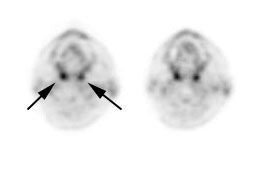

Head and neck activity: The images below show typical uptake in the tonsils (black arrows), submandibular glands (blue arrows), and parotid glands (red arrows) |

|

|